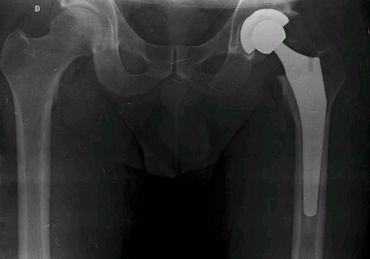

Artroplastía total de cadera no cementada izquierda